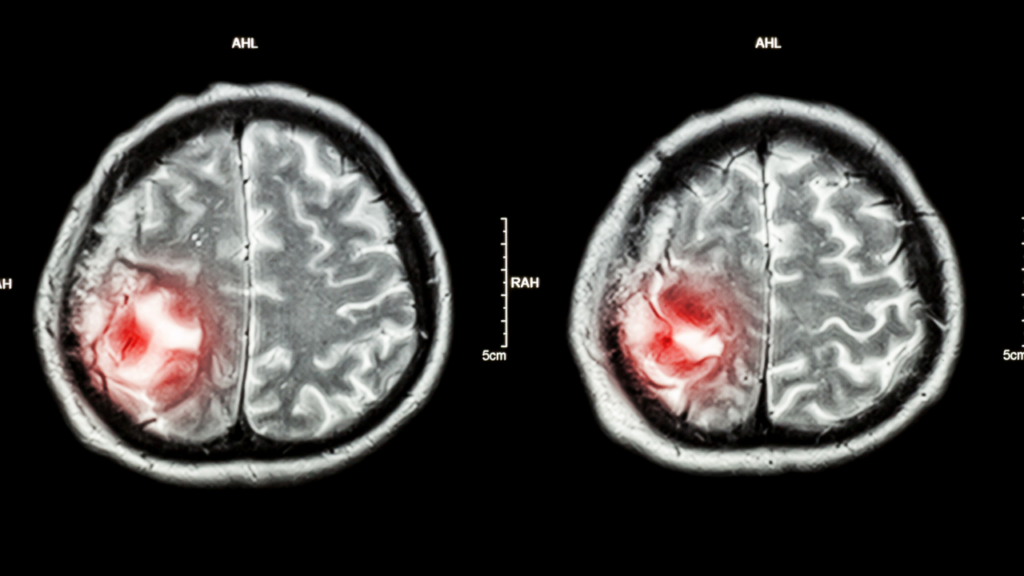

Beyin Tümörü Nasıl Teşhis Edilir?

Tanı süreci genellikle ayrıntılı öykü ve nörolojik muayene ile başlar. Ardından görüntüleme yöntemleri devreye girer. Manyetik rezonans görüntüleme çoğu durumda temel inceleme aracıdır; bazı hastalarda bilgisayarlı tomografi ve ek ileri testler de gerekebilir. Kesin tanı ve tümör tipinin belirlenmesi için bazı olgularda ameliyatla ya da biyopsi ile doku örneği alınması gerekebilir. Tanıda amaç yalnızca “kitle var mı?” sorusunu yanıtlamak değil; bunun hangi tip tümör olduğunu ve en uygun tedavi yolunu belirlemektir.

5) Beyin Tümörü Nasıl Teşhis Edilir?

Tanı süreci genellikle ayrıntılı öykü ve nörolojik muayene ile başlar. Ardından çoğu hastada MR gibi görüntüleme yöntemleri kullanılır; bazı durumlarda BT de gerekebilir. Eğer tümör saptanırsa, türünü daha net anlamak ve tedaviyi planlamak için ileri incelemeler veya bazı hastalarda biyopsi ya da cerrahi ile doku örneği alınması gerekebilir.